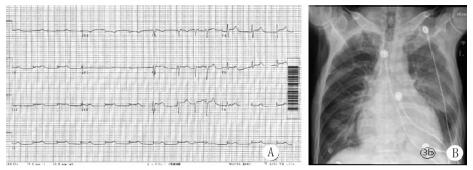

4月5日10:30患者胸痛症状明显减轻,测体温正常,血压103/78 mmHg。复查ECG(图 3A)示,非阵发性交界性心动过速,Ⅱ、Ⅲ、aVF、V4-V6导联ST仍抬高(0.1 mV);床边全胸片(图 3B)示,两肺渗出性病变,左侧胸腔积液。

A:心电图示:非阵发性交界性心动过速,Ⅱ、Ⅲ、aVF、V4-V6 导联ST抬高0.1 mV;B:床边全胸片示两肺渗出性病变,左侧胸腔积液 图 3 患者复查心电图和全胸片结果